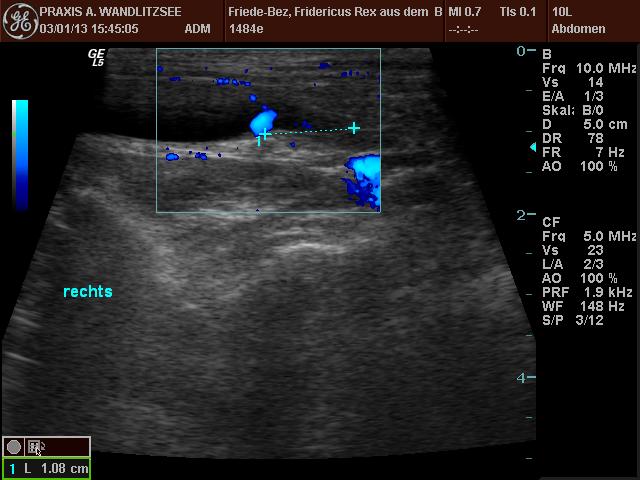

Die Ultraschalluntersuchung hat ein wenig länger gedauert als erwartet, da das harntreibende Mittel offenbar einige Zeit brauchte, seine Wirkung zu entfalten. Dann waren aber schöne "Jets" zu sehen, und zwar da, wo sie sein sollten. Grund zur Freude also. Welpi wurde die Zeit lang und er schlief ein, während der Doktor ihm mit dem Sonar über den Bauch fuhr.

20130103 Fridericus Rex eU Ultraschall rechts